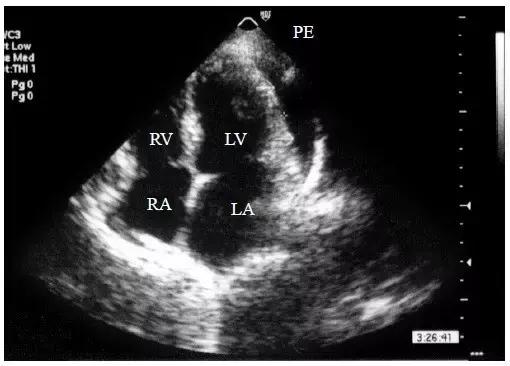

【少量心包积液】

液体仅潴留在左心室后壁和侧壁心包腔内,内径<10mm(图1)。

图1 少量心包积液的二维超声心动图表现

左心室后壁心包腔内少量液性暗区,内径< 10mm